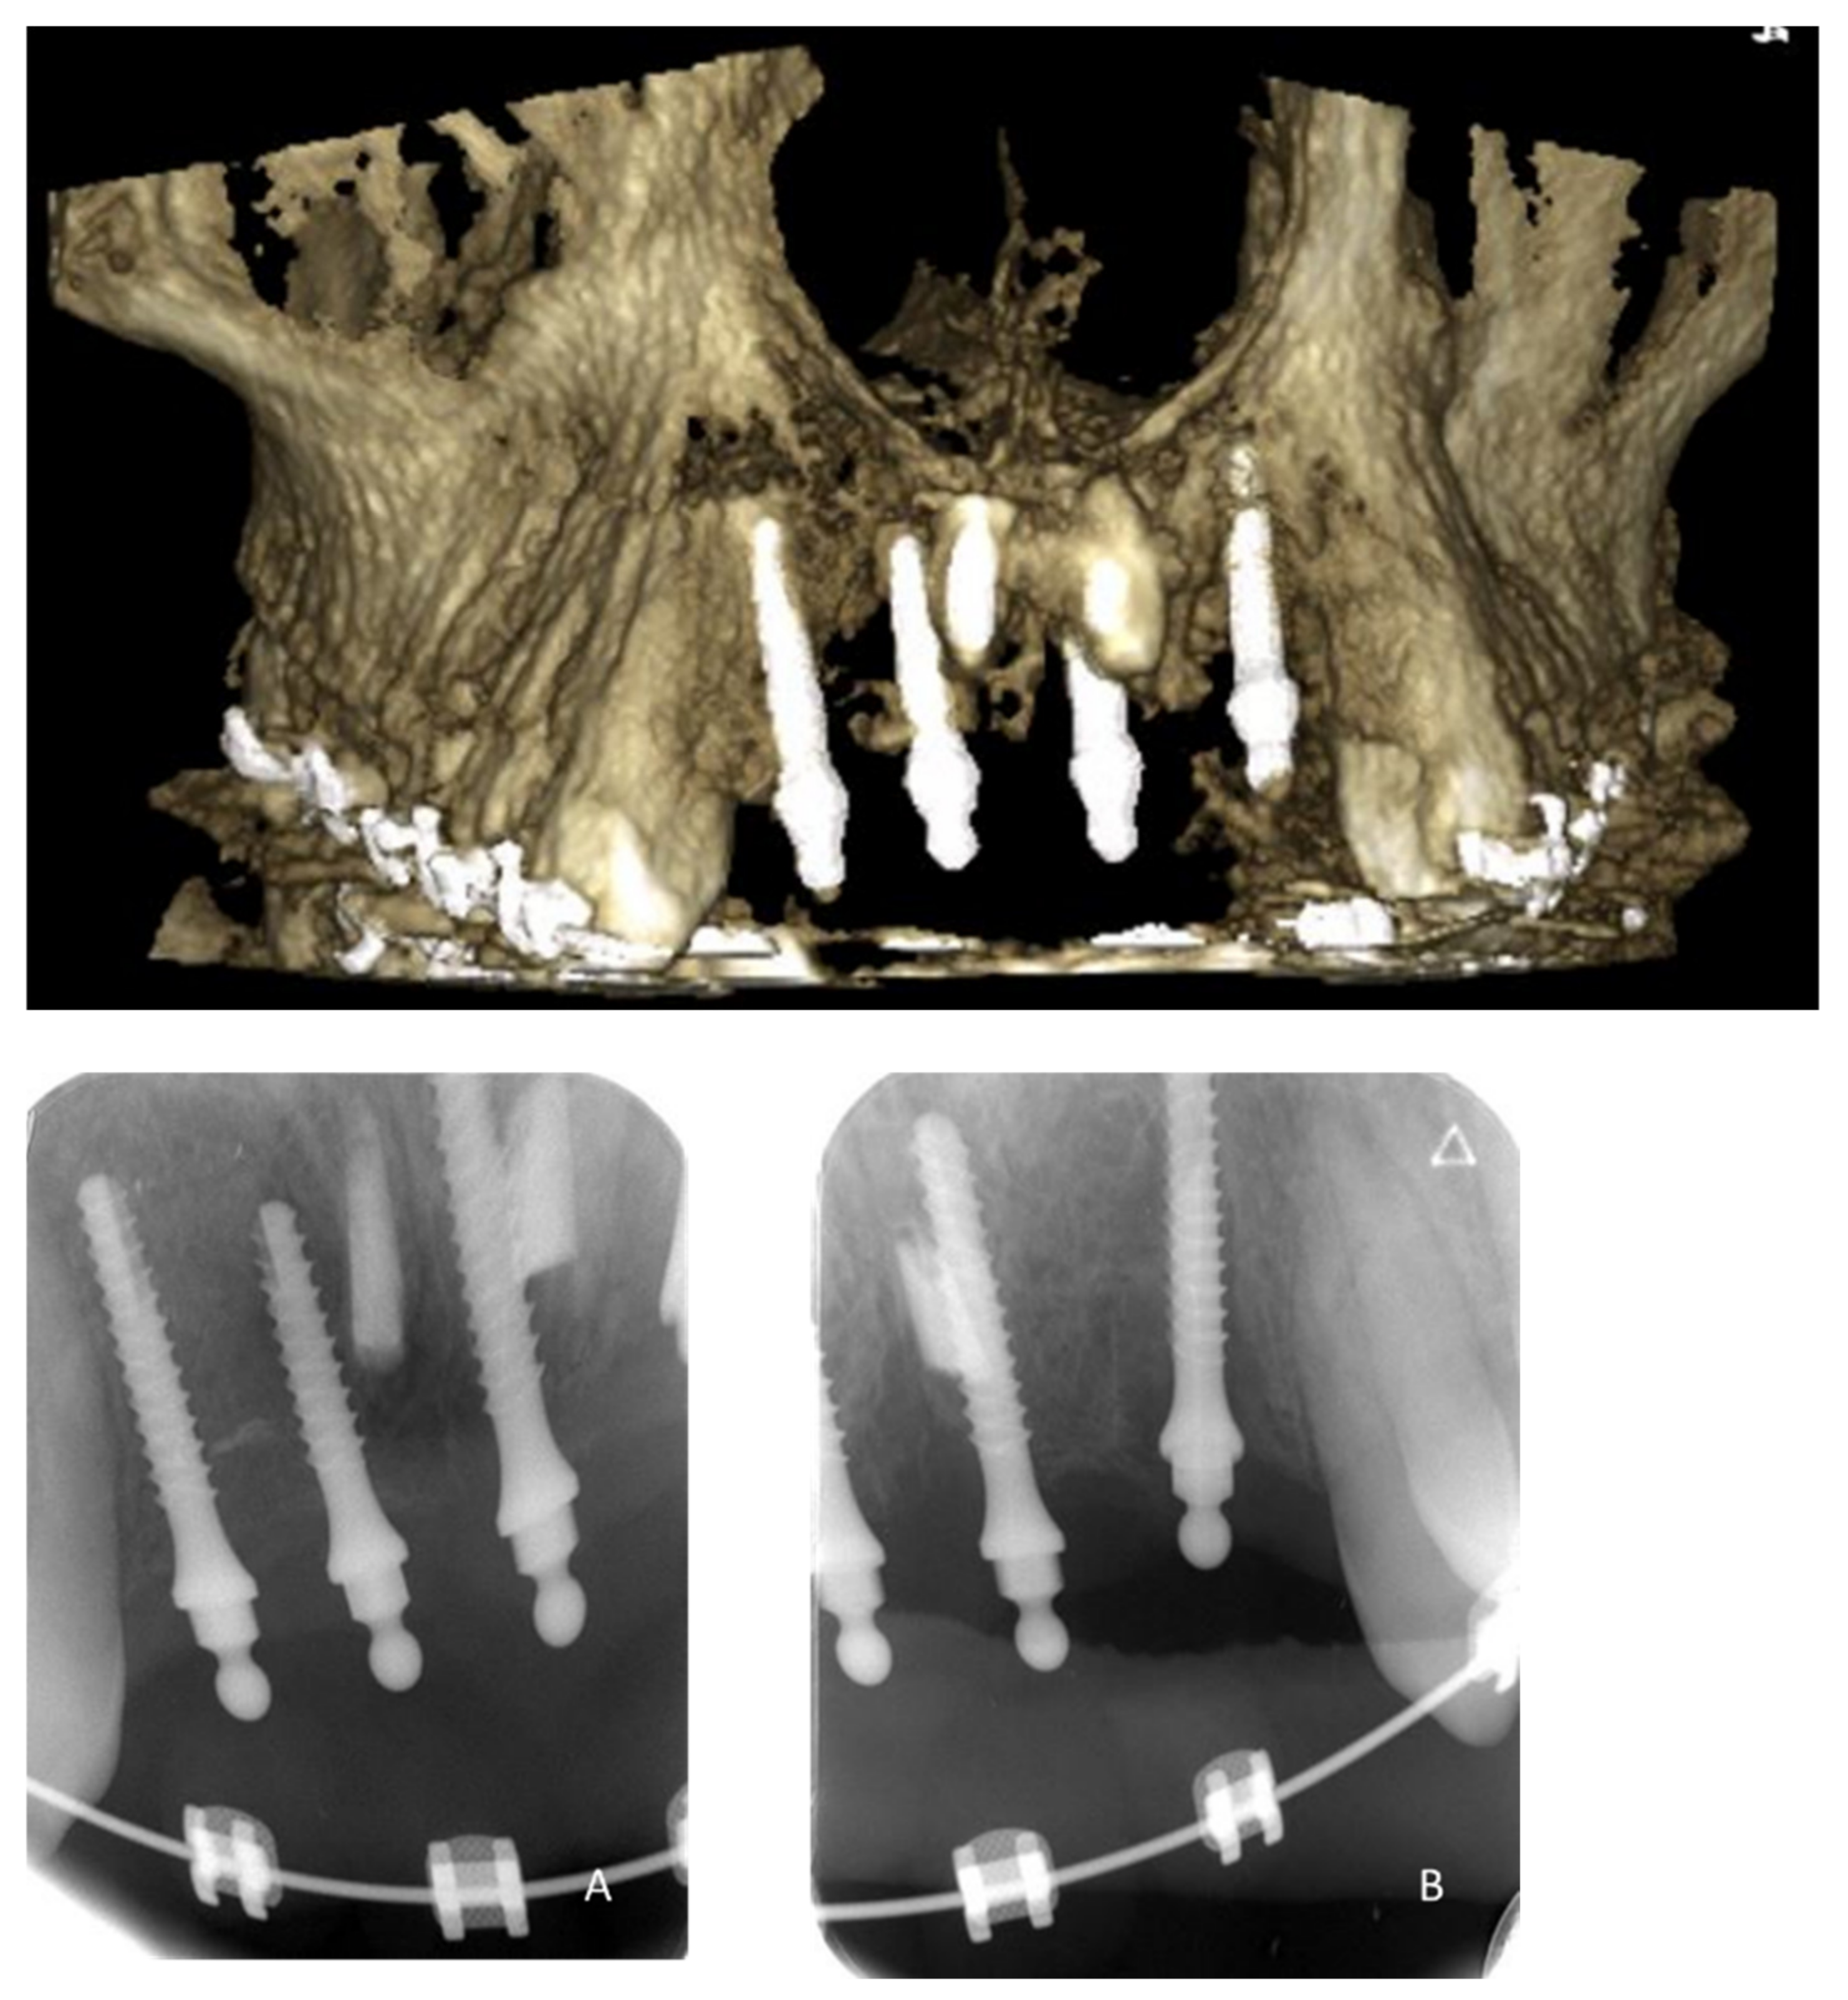

| May 2019: Orthodontic treatment for skeletal class II | Avulsion | |||

| Maintaining space for future implant replacement with resin crown temporization on the orthodontic arch | ||||

| Figure 8 | ||||

| Summer 2019 | Two infectious episodes despite an endodontic re-treatment | |||

| January 2020 | Avulsion | |||